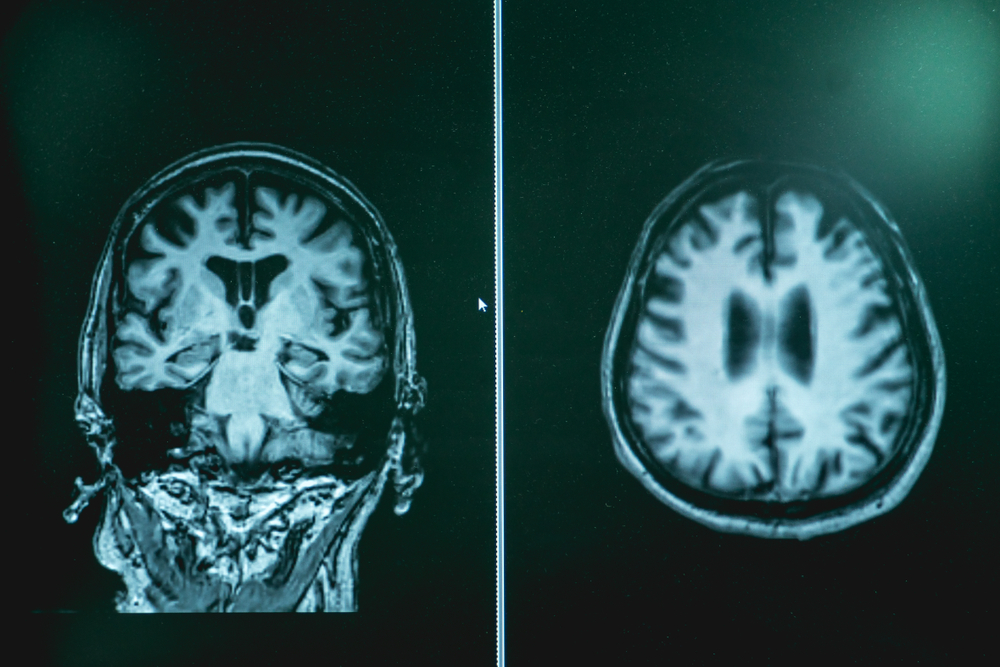

- Magnetic resonance imaging (MRI) maps out tissue using a contrast agent that allows sharp imaging detail.

All of these views help the care team sort patterns that match this disorder while ruling out other possible reasons for cognitive decline.